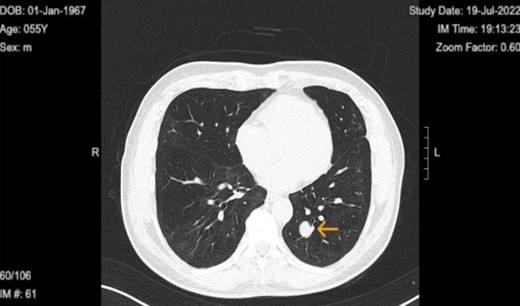

The patient is a 57-year-old male in the United States, who is a non-smoker with good past health. He had no history of occupational exposure to silica, beryllium, or asbestos. He presented with fever and dyspnea and attended the ER, where he was diagnosed with COVID-19 infection and a lung nodule. He underwent a computed tomography (CT) scan of the chest as a part of their diagnostic workup for suspected COVID-19 infection. Chest CT on 21 May 2021 revealed the presence of a well-demarcated non-calcified solid nodule of 1.5 × 1.3 cm in the left lower lobe of the lung (Fig. 1). It was suspected to be a lung carcinoma at first. CT-guided lung biopsy was recommended for further diagnosis.

Chest computed tomography in 2022 revealed well circumscribed solitary lung tumor of 1.5 × 1.3 cm in size.